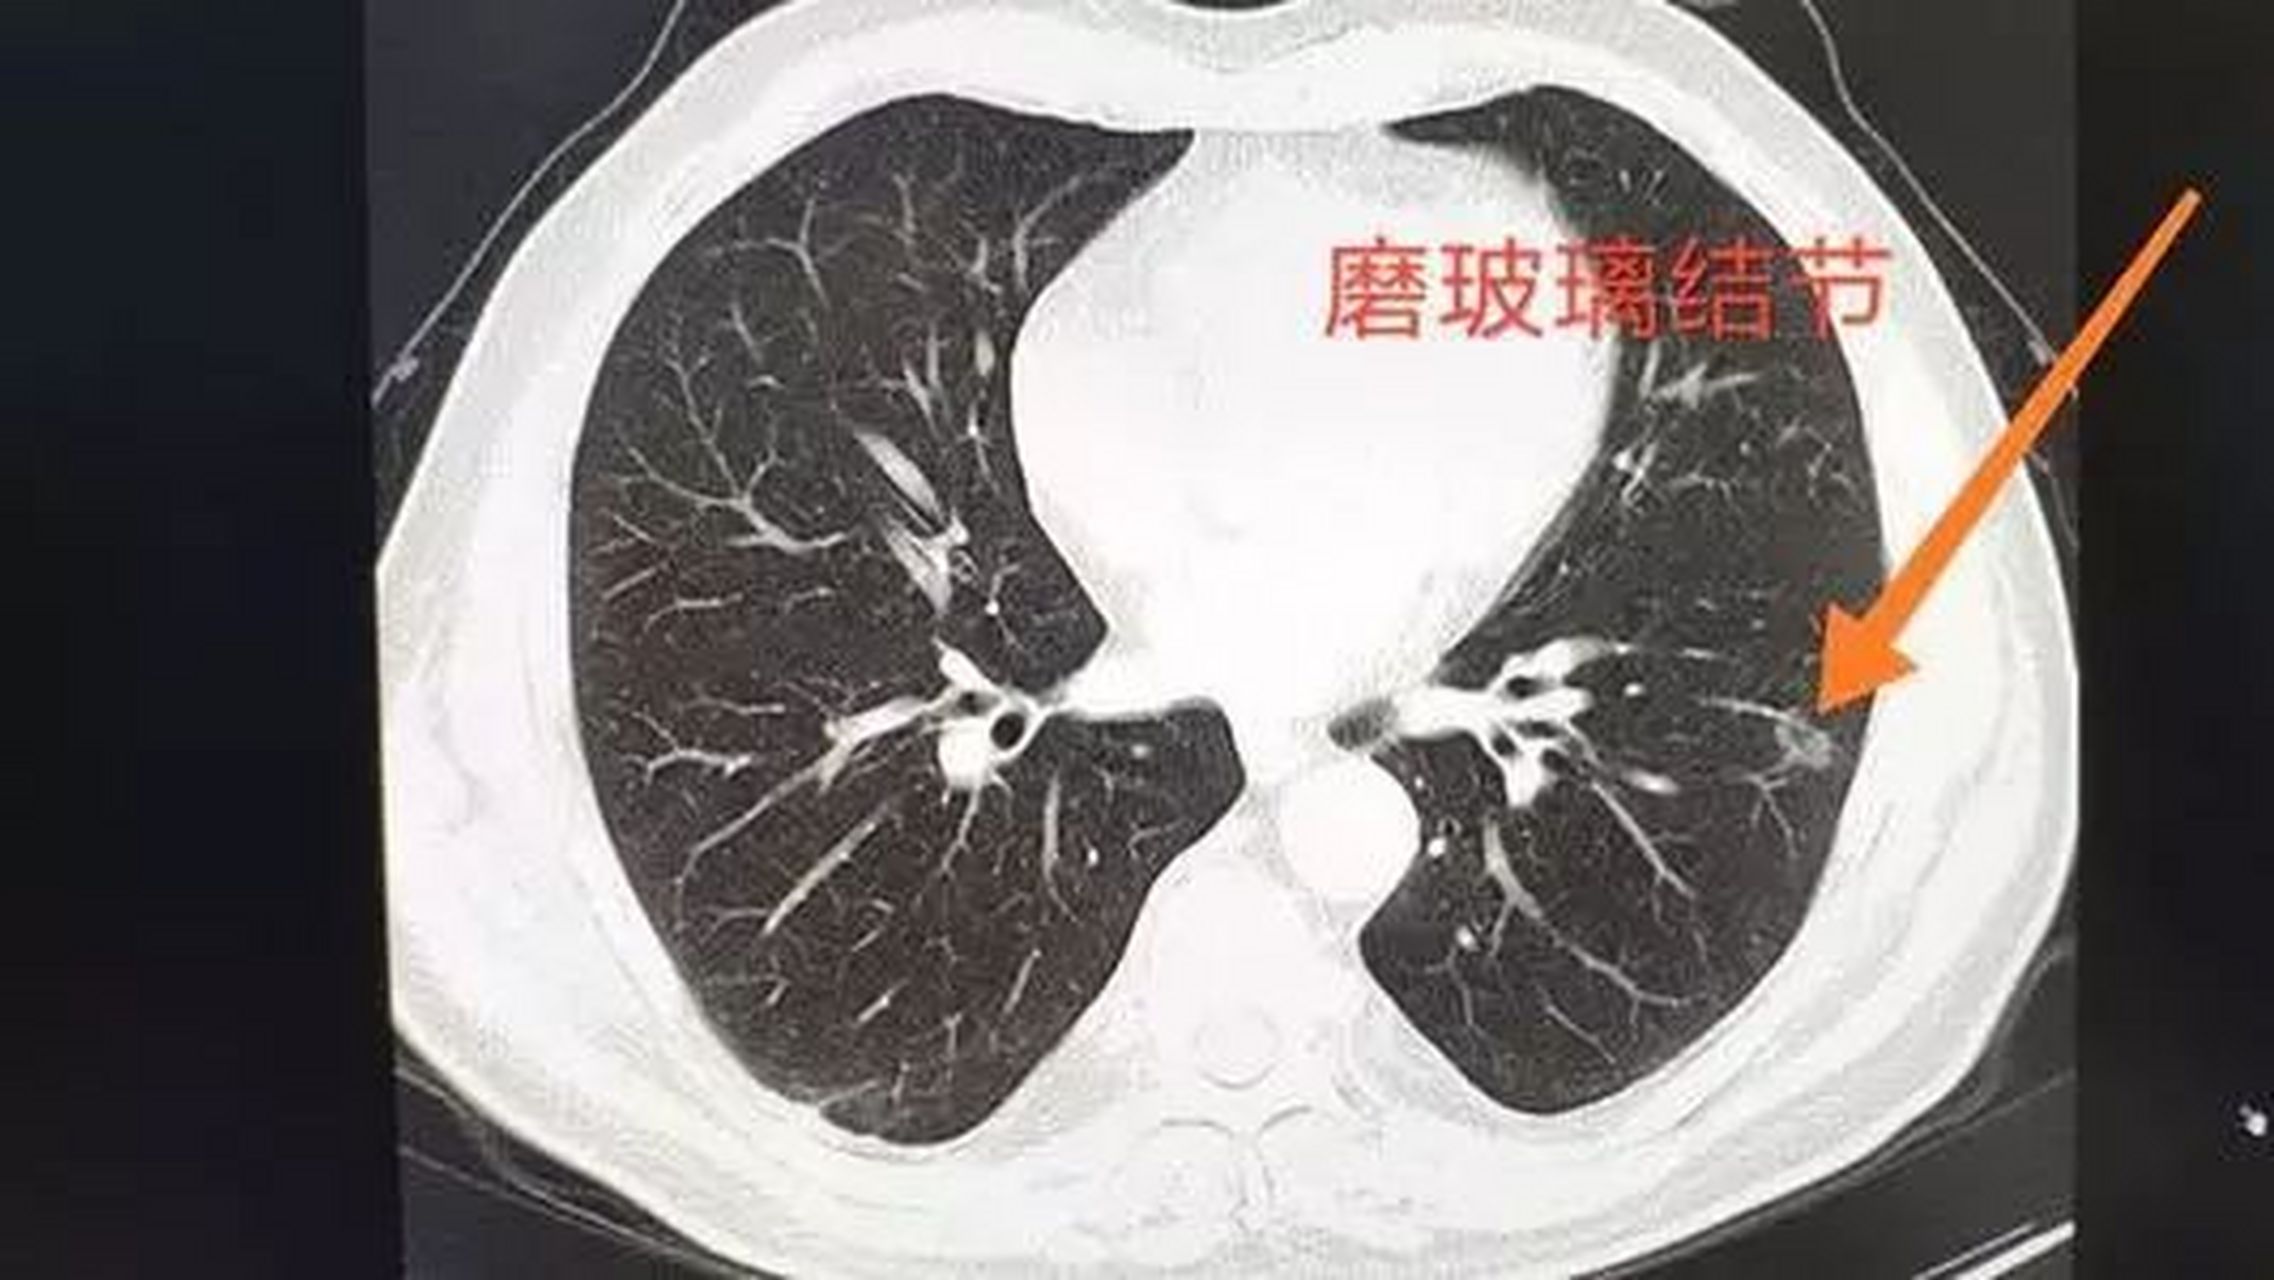

核保实例磨玻璃肺结节6mm重疾险除外承保

图片尺寸1080x547